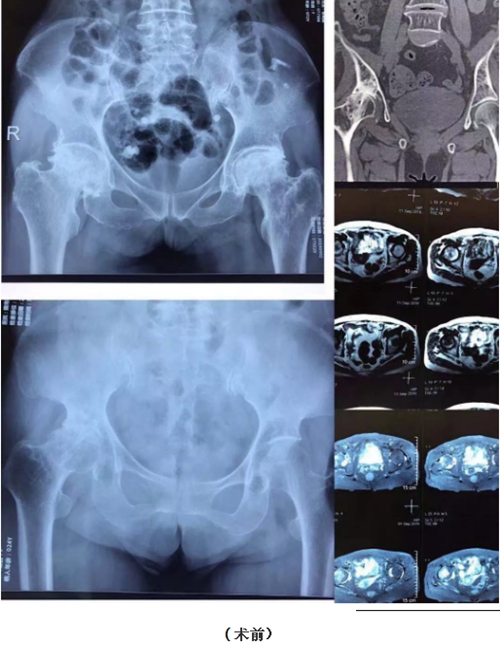

患者宋某,女,76岁,因右侧髋关节疼痛1年,加重1月入住骨一科。入科后查体示:右下肢短缩畸形,右髋关节屈曲、外展及旋转活动受限,4字试验阳性,行走后跛行,末梢循环及感觉未见异常。初步诊断为:股骨头缺血坏死。

患者苏某,女,73岁,双侧髋部疼痛3年余。查体:双侧髋关节活动受限,右髋关节为甚,双侧髋关节4字试验阳性,末梢循环及感觉未见异常。入院后诊断为:双侧股骨头缺血性坏死。